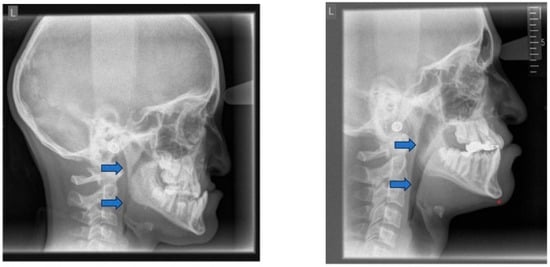

Headgear treatment is used for skeletal Class II correction by affecting the anterior–posterior position of the maxilla. Cervical headgear, used for at least 12 h daily with an average force of 450 g per side for one year, can effectively restrict anterior maxillary growth [163,164,165,166,167] (Table 1). This restriction may have an adverse effect on the dimensions of the nasopharyngeal airway and the intraoral tongue space. Children receiving combined activator-headgear treatment for skeletal Class II correction presented a significant negative impact on sagittal development of the maxilla (reduction of SNA angle: angle defined by nasion-sella-point A), when compared to controls without headgear treatment [168]. Thus, treatment with headgear may contribute to alterations in the dimensions of the nasopharyngeal and oropharyngeal airway [169]. A further study concluded that headgear treatment may even contribute to OSA during nighttime wear. Therefore, headgear treatment in children with retrognathic mandibles should be carried out with caution. If a patient already presents with OSA, headgear treatment may aggravate OSA [170] (Figure 16).

9.3. Craniofacial Adverse Effects of Continuous Positive Airway Pressure (CPAP) Therapy

Even if there are clear benefits to CPAP therapy, when it is implemented at a very young age, flattening of the midface or maxillary retrusion due to prolonged mask pressure may occur, and it must be carefully monitored [126,171]. This may reduce nasopharyngeal airway and intraoral volume, leading to a lower tongue (rest) posture and potentially affecting the orofacial development. Additionally, unwanted tooth movement is a further side effect of CPAP therapy, which can impact quality of life [172].

These dental and skeletal side effects may impact both function and aesthetics, highlighting the need for orthodontic monitoring in children undergoing prolonged CPAP therapy.